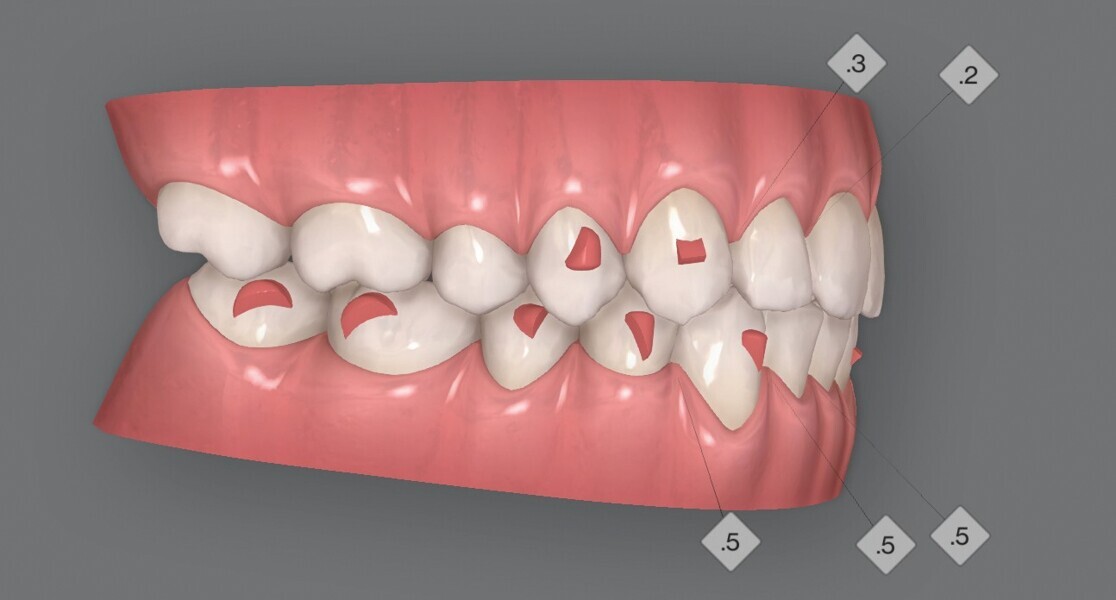

Fig. 4a : Premier résultat prévu par simulation ClinCheck.

Fig. 4b : Premier résultat prévu par simulation ClinCheck.

Fig. 4c : Premier résultat prévu par simulation ClinCheck.

Fig. 4d : Premier résultat prévu par simulation ClinCheck.

Fig. 4e : Premier résultat prévu par simulation ClinCheck.

Le premier plan de traitement par simulation ClinCheck prévoit 53 aligneurs, afin de réaliser une distalisation séquentielle postérieure d’environ 4 mm sur le côté gauche du maxillaire, une expansion de 2 mm par quadrant et un alignement dans la zone antérieure. Il prévoit également une réduction interproximale (RIP) sélective de 0,25 mm sur chaque face des dents de l’arcade mandibulaire, et de 0,10 mm à 0,15 mm pour les dents de l’hémiarcade maxillaire droite (Fig. 4). Une application topique de fluorure est planifiée dans les zones soumises à une RIP après la procédure. Des élastiques de classe II sont utilisés du côté gauche pour faciliter la distalisation. La fréquence de changement des aligneurs est fixée à sept jours et elle sera ramenée à cinq jours par la suite. Un accélérateur de traitement orthodontique par vibrations est utilisé, afin d’augmenter la vitesse et la prédictibilité des mouvements dentaires. Le traitement n’envisage pas l’utilisation d’aligneurs de surcorrection.